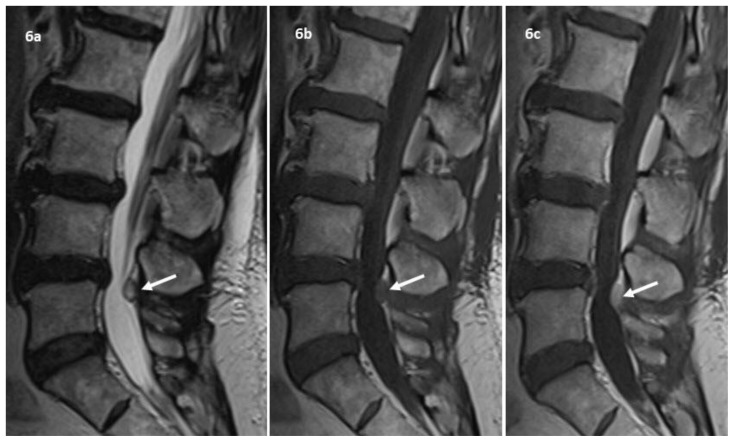

Figure 6.

60-year-old lady with resected clival chordoma and new drop metastasis.

Findings: MRI whole spine was done to screen for other drop metastases. (a) Sagittal T2W image showed another well circumscribed hyperintense nodule in the posterior epidural space at the L4–5 level. (b) The nodule is isointense on T1W sequence and (c) demonstrates homogenous contrast enhancement. This was also deemed to be a metastasis as the dura had been breached during the transphenoidal surgery.

Technique: 1.5T Siemens MAGNETOM Aera MRI scanner

a) Sagittal T2W. TR 5000. TE 98. 3mm slice thickness.

b) Sagittal T1W pre-contrast. TR 577. TE 8. 3mm slice thickness.

c) Sagittal T1W post-contrast. 10ml intravenous Dotarem. TR 577. TE 8. 3mm slice thickness.

Post-operative follow-up imaging showed no residual enhancing tumor in the sella. Staging CT showed no distant metastasis. The patient then underwent adjuvant radiotherapy. About 11 months after surgery, a new small round, homogenously enhancing intradural extramedullary solid nodule was visualized in the anterior foramen magnum, indenting the medulla oblongata on a surveillance MRI (fig. 5). This lesion showed similar signal characteristics as the index tumor with intermediate signal intensity on T1-weighted images and high signal intensity on T2-weighted images and was deemed to be a drop metastasis. MRI whole spine which was performed to look for other drop metastases found another similar appearing nodular lesion in the posterior epidural space at the L4–5 level (fig. 6), also suspicious for metastasis. The patient was asymptomatic from the metastases and decision was made for expectant management following discussion in a multidisciplinary tumor board and consultation with the patient.